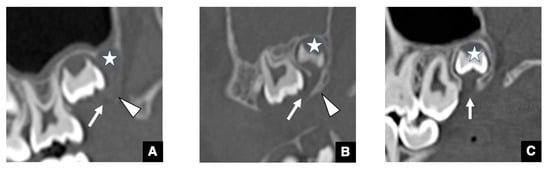

2.2. CT Images of GT in Accessional Tooth